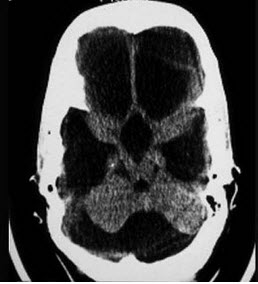

根据CT表现考虑为( )

A:Dandy-Walker综合征

B:Arnold-Chiari畸形

C:颅底凹陷症

D:大脑导水管狭窄

E:上矢状窦血栓形成